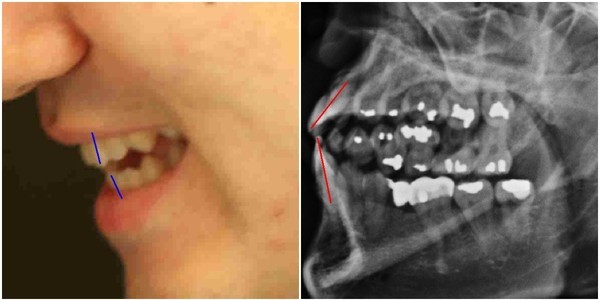

김우현씨는 박주신씨가 자생병원에서 MRI를 촬영하면서 함께 찍은 엑스레이 사진에 의문을 나타냈다.

박주신씨의 치아가 보이는 ‘구외 엑스레이’(이하 치아 엑스레이) 사진에서 나타나는 피사체의 치아상태는 불량하기 짝이 없었다.

도저히 중산층 가정의 20대 청년의 것으로 볼 수 없을 만큼 치아상태가 나빴다.

-

- ▲ 박주신씨 명의의 치아 엑스레이 사진. ⓒ 뉴데일리DB

김우현씨는 서울 방배동에 살던 20대 청년이 무려 14개에 이르는 치아를 아말감으로 치료 하고, 일부 치아는 아예 빠진 채 몇 년간 방치된 사실에 고개를 가로저었다.

아말감은 수은증기 논란과 변색의 문제점 등으로 1990년대 들어 사용빈도가 급감했다. 2005년경 서울의 중산층 청년이 하나도 아닌 무려 14개의 치아를 아말감으로 치료한다는 것은 상식 밖이었다.

김우현씨는 치과의사로서의 임상경험을 근거로, 자생병원 엑스레이 피사체의 정체에 의문을 가졌다.